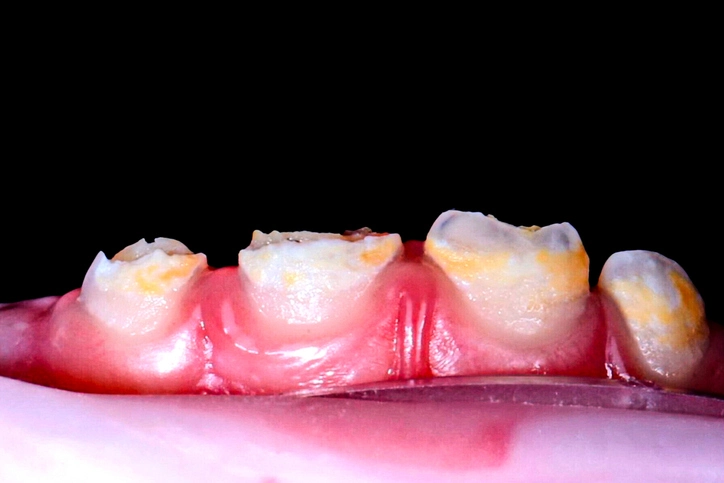

2. Hypocalcified Amelogenesis Imperfecta

Features:

- Enamel thickness is normal at eruption but soft and chalky.

- Color ranges from yellow-brown to honey-colored.

- Rapid post-eruptive wear and calculus accumulation are common.

- Teeth are extremely sensitive due to exposed dentin.

- Inheritance may be autosomal dominant or recessive.